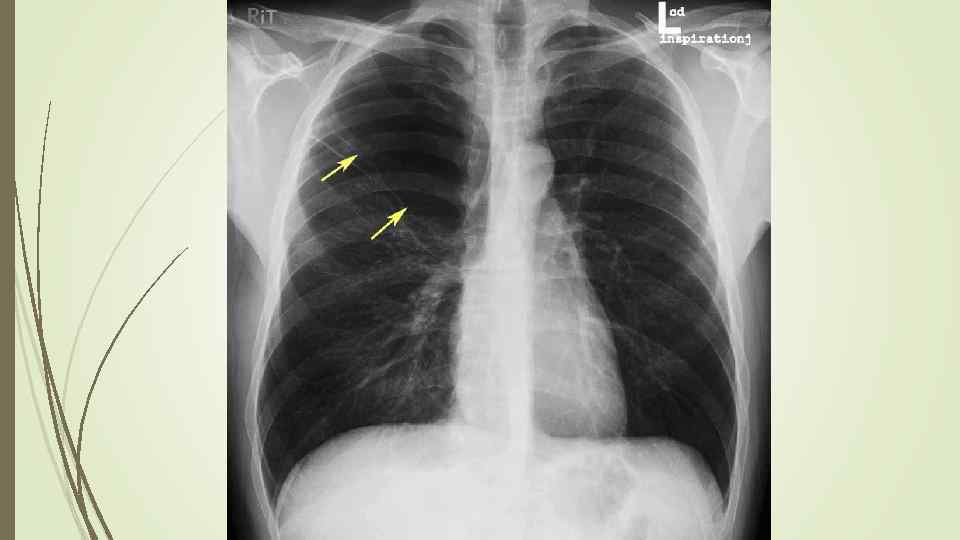

Пневмоторакс – скопление газа в плевральной полости, ведущее к спадению ткани легкого, смещению средостения в здоровую сторону, сдавлению кровеносных сосудов, опущению купола диафрагмы, что, в конечном итоге вызывает расстройство функции дыхания и кровообращения. Различают травматический, спонтанный и ятрогенный пневмоторакс. В зависимости от наличия связи с окружающей средой различают закрытый, открытый и клапанный пневмоторакс.

Пневмоторакс – скопление газа в плевральной полости, ведущее к спадению ткани легкого, смещению средостения в здоровую сторону, сдавлению кровеносных сосудов, опущению купола диафрагмы, что, в конечном итоге вызывает расстройство функции дыхания и кровообращения. Различают травматический, спонтанный и ятрогенный пневмоторакс. В зависимости от наличия связи с окружающей средой различают закрытый, открытый и клапанный пневмоторакс.

Рентгенологическое исследование: свободный газ в плевральной полости (участок просветления, лишенный легочного рисунка, расположенный на периферии легочного поля, на фоне пневмоторакса отчетливее, чем обычно, видны детали костного скелета грудной клетки) поджатое лёгкое, степень спадения которого зависит от величины пневмоторакса при напряжённом пневмотораксе средостение смещается в здоровую сторону.

Рентгенологическое исследование: свободный газ в плевральной полости (участок просветления, лишенный легочного рисунка, расположенный на периферии легочного поля, на фоне пневмоторакса отчетливее, чем обычно, видны детали костного скелета грудной клетки) поджатое лёгкое, степень спадения которого зависит от величины пневмоторакса при напряжённом пневмотораксе средостение смещается в здоровую сторону.